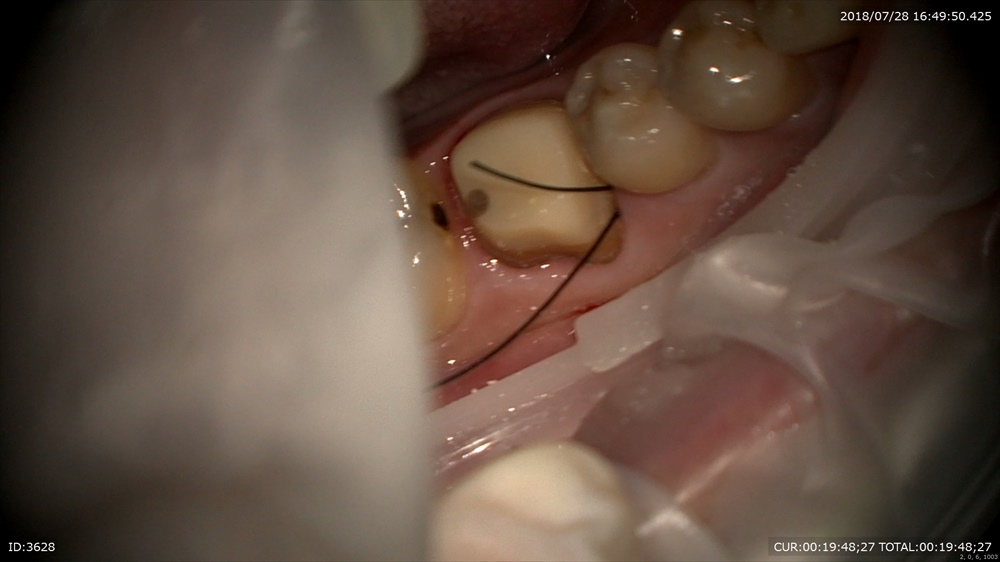

今日の患者さん。この方は他院の根管治療後腫れて治らず今年の年始にいらして頂きました。

歯科ドックの結果

歯周病治療、根管治療、土台、被せ物のやり直しが必要でした。

細かく根管治療

手間ヒマかけて

23倍でバイオフィルムを取り

土台をたて

仮歯で半年様子見

初診の腫れも消え症状もなく、患者さん

「抜歯しなくて良いのですね」

と喜んでいました。